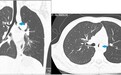

术前CT检查,箭头处为肿物

今年9岁的小琪本应在校园里追逐嬉戏,但近一个月却持续地咳嗽咳痰,严重影响了她的学习生活。家人带小琪前往医院就诊,完善胸部增强CT后才发现罪魁祸首——左主支气管有一个1.5X1.1X1.0cm的肿物。经多方打探,孩子父母得知广州妇儿中心胸外科李乐主任团队对儿童气管手术有丰富的诊疗经验,于是前往我院胸外科进一步治疗。

入院后,李乐主任团队为小琪完善了胸部CT和纤支镜检查,发现肿瘤位于气管隆突附近,几乎将左主支气管完全堵住,如果肿瘤再侵犯气管隆突或者右主支气管,就会有窒息的危险。针对小琪的病情,胸外科迅速组织麻醉科、呼吸科、PICU、影像科等多学科会诊和讨论,决定尽快手术治疗,切除气管肿瘤并重建气管。